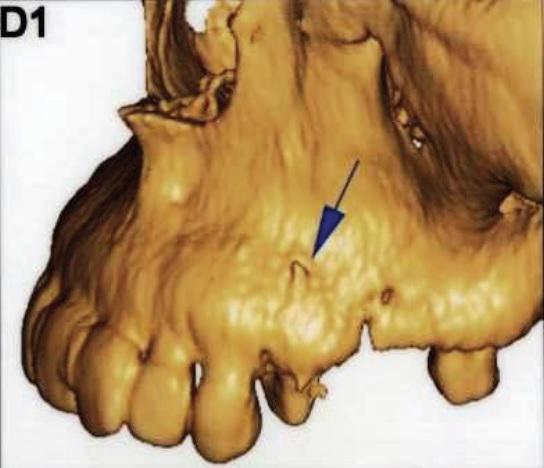

Полость корневых каналов промыли физиологическим раствором и восстановили зуб с помощью материалов для временного пломбирования. Чтобы предотвратить риск инфекции, в течение трех дней внутримышечно пациентке вводили клиндамицин (600 мг дважды в день), и также назначили ибупрофен (400 мг) для купирования боли, который она принимали по мере необходимости. Экстренное наружное использование холодных компрессов в первый день сменили на теплые компрессы во второй день для лечения отека. На первом повторном визите отмечалось увеличение кровоподтека, хотя припухлость значительно уменьшилась (фото 3). Отек и кровоподтек постепенно исчезали в течение всего периода наблюдения, а на 10 день после процедуры у пациентки исчезли все беспокоившие ее симптомы (фото 4). Для оценки соотношения между зубом, альвеолярным отростком и верхнечелюстной пазухой была проведена дентальная объемная томография (dental volumetric tomography — DVT) (NewTom 3G, QR SRL, Верона, Италия). На DVT-изображении было обнаружено, что апекс щечного корня перфорирует кортикальную пластинку верхнечелюстной кости, создавая, таким образом, свободный путь для проникновения ирригационного раствора в мягкие ткани (фото 5 (а) и фото 5 (б)). Через 10 дней симптомы полностью исчезли. В то же время в корневой канал наложили повязку с гидроксидом кальция. Во время заключительного посещения примерно через 4 недели после предыдущей процедуры корневые каналы запломбировали материалом AH Plus (Dentsply Maillefer) и гуттаперчей (фото 6).

Фото 5: (а) Изображение 3D и (б) коронарный вид DVT показали, что верхушка щечного канала перфорирует кортикальную пластинку верхней челюсти.